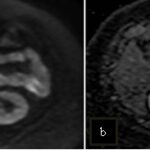

Mujer de 36 años que ingresa a Hospital Sanatorio Franchin el 11 de octubre de 2023 de forma programada para realización de duodeno pancreatectomía cefálica por tumor de cabeza de páncreas en estudio. Refiere hallazgo de lesión en forma incidental durante estudio de control hace dos meses por presentar antecedentes familiares (neoplasia endocrina múltiple). Se interna para manejo quirúrgico. Estudios de tomografía revelan formación nodular localizada en cabeza y cuerpo pancreático de paredes gruesas que mide 24 x 28 mm, que en resonancia se muestra hiperintensa en T2 y realce periférico luego de la administración de contraste endovenoso. Presenta restricción en la difusión con caída de la señal ADC, por lo que se vincula con una lesión de alta celularidad.

La resonancia magnética es el otro estudio de imagen no invasivo que nos permite la detección de la lesión con una sensibilidad mayor que la de la tomografía, del 85% al 95%, donde los insulinomas presentan un realce tras la administración de contraste con gadolinio y secuencias T1 sin contraste son lesiones hipointensas y en secuencias T2 son hiperintensas.

La resonancia magnética confirmó aún más el diagnóstico de las lesiones ya previamente visualizadas en tomografía en esta revisión, con realce de las lesiones en secuencias T1 y contraste con gadolinio, y en las secuencias funcionales con restricción de la lesión y caída de la señal en el mapa de ADC.